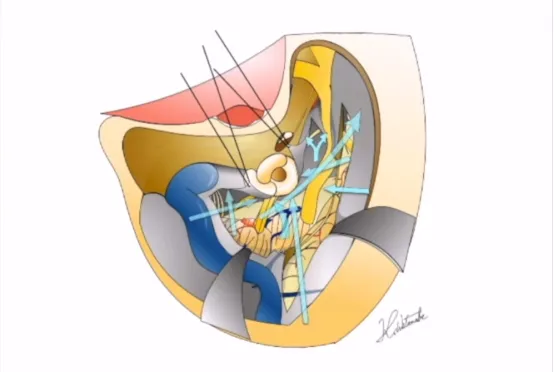

中颅窝被平整化,然后我们逐渐识别出棘孔。中脑膜动脉被凝固并切断。对硬脑膜进行剥离,逐渐识别出三叉神经半月节(GSPN)、第三叉神经(V3)、弓状隆起和岩嵴,这些是Kawase菱形区的边界。

在脑组织紧张的情况下,打开retrosigmoid区的硬脑膜,以访问颅底神经池并释放脑脊液(CSF)。Kawase菱形区的钻孔应从最安全的区域开始,即靠近V3的位置,在那里创建一个孔洞。然后这个空腔在持续冲洗的情况下,向后和后外侧方向逐渐扩大,直到暴露出后颅窝的硬脑膜。随后,前岩骨切除术向下和向后延伸,直至达到围绕耳蜗和上半规管的皮质象牙骨。

早在2019年,福教授就曾发布论文《How I do it:combined petrosectomy》,创新了联合岩骨切除术。联合岩骨切除术和横窦-乙状窦后移位,能够在减少对大脑的牵拉损伤的同时,在较短的距离下广泛暴露大型岩斜坡病变,并提供多个操作角度,为腹侧脑干、中上部斜坡等提供宽广的手术空间。